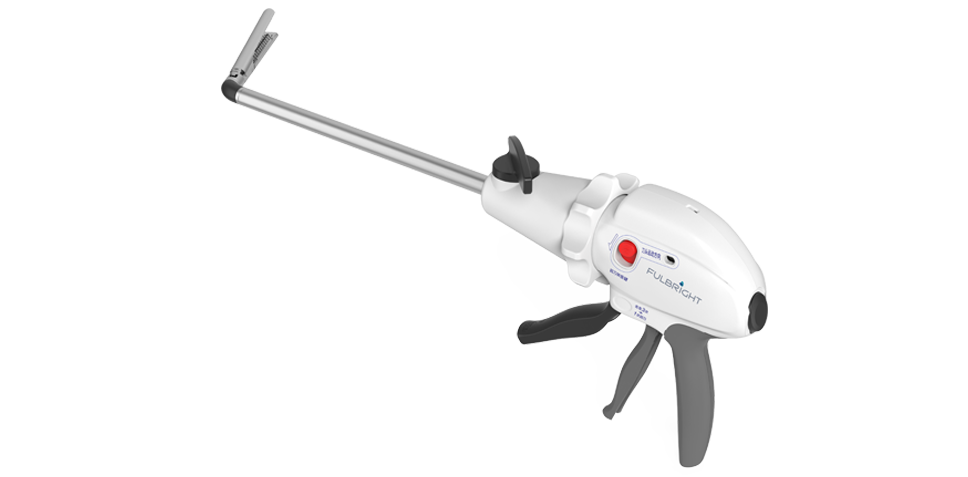

握持轻松,便于施力,更适合东方人和女性术者

自由角度调节,可形成大角度操作维度,适用于狭窄的手术操作部位

率先推出关节无级转弯技术

钳口打开和关闭时,均可实现转弯,操作自由

旋钮键调节角度,简单易懂

产品名称:一次性使用腔镜切割吻合器及组件